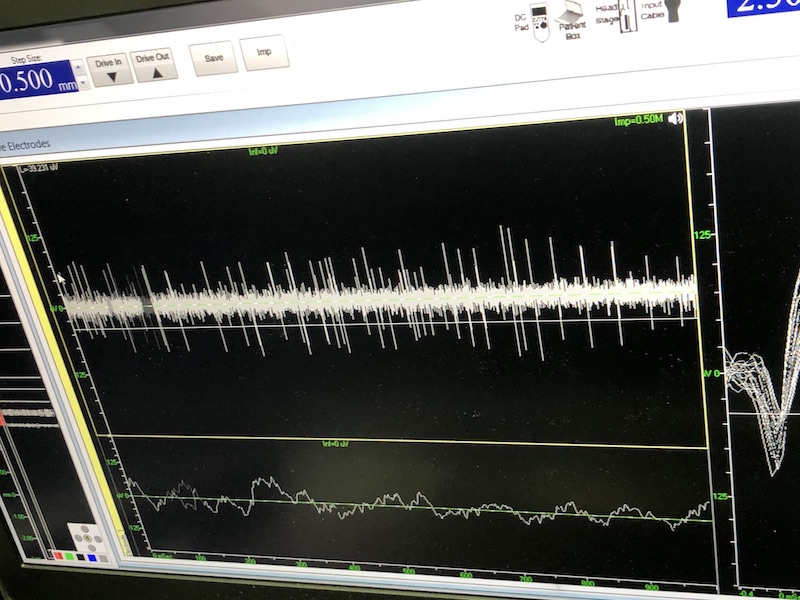

與此同時(shí),檢測(cè)電極實(shí)時(shí)記錄電極末端每一點(diǎn)處的電信號(hào),當(dāng)電極逐漸接近手術(shù)規(guī)劃靶點(diǎn)時(shí),借助電信號(hào)的特征,醫(yī)生可以判斷電極是否已經(jīng)沿長(zhǎng)軸植入患者顱內(nèi)的目標(biāo)核團(tuán),以及植入的準(zhǔn)確長(zhǎng)度。下圖中,檢測(cè)信號(hào)屬于典型的核團(tuán)信號(hào),證明電極已經(jīng)抵達(dá)相對(duì)理想的植入位置,記錄下此刻的位置后,即可在相應(yīng)位置植入刺激電極。

檢測(cè)核團(tuán)信號(hào)